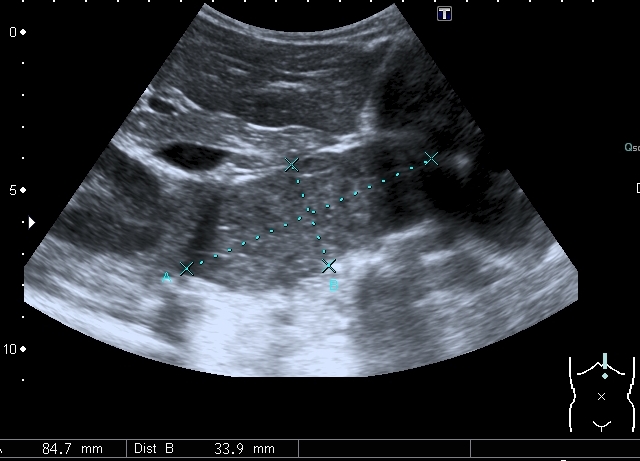

Предлагаю интересные изображения, полученные при сканировании лёгких через межрёберные промежутки и печень у ребёнка 4-х лет с подозрением на пневмонию

участок безвоздушной легочной ткани....похож на печень...пневмония в стадии опеченения... ;)

Согласен в отношении нижней доли правого лёгкого, изменения в ней похожи на сливную инфильтрацию при пневмонии, хотя носят несколько многоузловой характер. Но то что мы видим со спины в левом лёгком на пневмоническую инфильтрацию не похоже.

Добавляю сканы печени, я думаю они являются хорошей подсказкой о природе изменений в лёгких